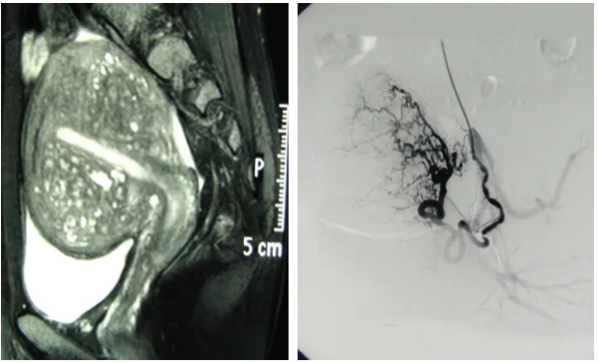

可以将子宫腺肌症的病灶理解为一个需要血液供应才能生长和引起症状的组织。介入治疗通过向供养病灶的血管内注入微小的栓塞颗粒,从而减少或阻断其血液供应。血液供应减少后,病灶因缺乏养分而逐渐萎缩、纤维化,相关症状也因此可能得到缓解。

2. 精准导航:在数字减影血管造影(DSA)设备的实时引导下,将一根纤细柔软的导管,经血管系统精准送达子宫的供血动脉。

3. 靶向栓塞:通过导管,将大小适宜的栓塞颗粒注入目标血管。这个过程是可控且可视的。